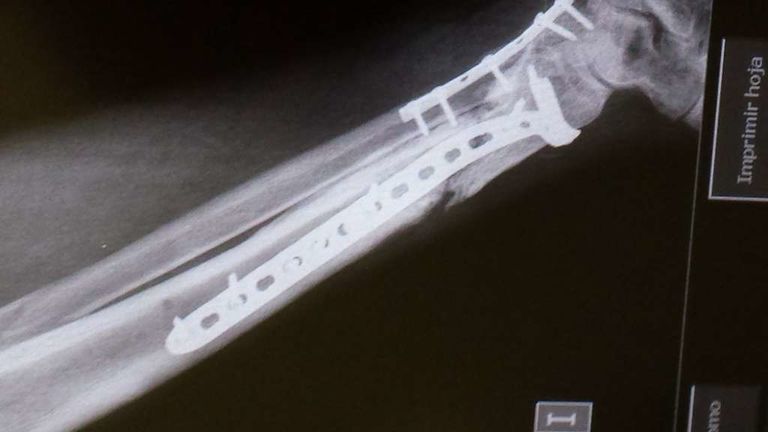

Mito Publicado 19 de Noviembre del 2014 Compartir Publicado 19 de Noviembre del 2014 Yo tuve un accidente de moto y me rompí la tibia y el peroné. Me tubieron que poner un clavo como el has puesto en las fotos y aún lo llevo, esto fue en el 2002 y ha dia de hoy no me molesta ni me lo voy a quitar. La rehavilitación fue muy muy lenta uffff y eterna. Estuve 3 meses sin poder poner el pie en el suelo, con muletas, la pierna se me quedó sin fuerza ninguna. En rehabilitación no notaba mejoría... creo recordar que pasó un año para que yo estuviera caminando normal. Me apunté a un gimnasio y ahí fue cuando recuperé toda la fuerza. Mucha paciencia y echarle muchas ganas de recuperación y siento mucho lo que te ha pasado, por que es superdoloroso y muy pesado -sombrero Enlace al comentario Compartir en otros sitios web More sharing options...

SuperGabaDink Publicado 19 de Noviembre del 2014 Compartir Publicado 19 de Noviembre del 2014 Mucho animo y paciencia compi! Me sumo a Mito ya que me paso algo parecido aunque tarde un poco mas...Una buena rehabilitación sumada a la que le eches tu aparte es la clave. A eso sumale una buena dosis de animo y positivismo pensando que te pondras bien aunque el proceso sea lento, y ya sera historia pasada. Yo me rompi tambien tibia y perone al caerme el scooter encima de mi pierna. La tibia en 3 cachos,desplazada,astillada etc...casi pierdo la pata. Llevaba mas hierros que Robocop y un sin fin de operaciones con injertos variados..jejeje; tarde 2 años en recuperarme,3 en olvidarme del tema y no cojear y 4 en poder volver a poner mi culo en una moto... No te desanimes,ya veras como en nada podras darle gas de nuevo. Enlace al comentario Compartir en otros sitios web More sharing options...

Andres1108 Publicado 19 de Noviembre del 2014 Compartir Publicado 19 de Noviembre del 2014 Solo con ver las radiografias me duele todo... Animo! Piensa que luego serás un motero bionico... mejorado artificialmente jajaja Un saludo Enlace al comentario Compartir en otros sitios web More sharing options...

jerolo Publicado 31 de Enero del 2016 Autor Compartir Publicado 31 de Enero del 2016 El lunes 1 placa y a ver como va la cosa,subiré foto PD. Cómo me duele la puta pierna :-) Enlace al comentario Compartir en otros sitios web More sharing options...